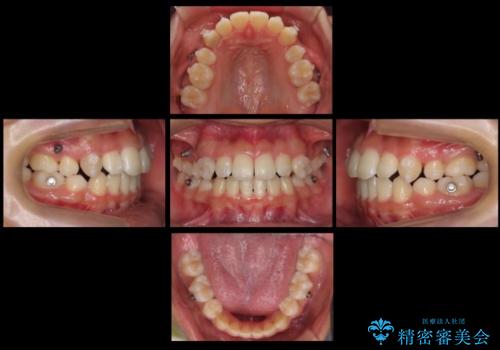

八重歯や抜歯したスペースの閉鎖をワイヤー矯正で前半行い、治療後半は目立たないインビザラインでかみ合わせを調整しました。

ワイヤー矯正からインビザラインへの変更は、歯磨きも簡単になり、目立たず、さらにワイヤーと併用することで妥協せずしっかり治療結果も出すことができます。

上の奥歯を後ろ下げるために、矯正用ミニスクリューを使用しています。